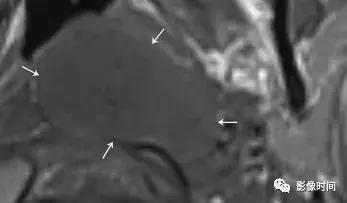

3、脑膜瘤:脑膜瘤是中枢神经系统最常见的脑外颅内肿瘤,大多数脑膜瘤发生在颅内。颈静脉孔区的脑膜瘤可向下延伸至颈动脉间隙。大多数脑膜瘤 CT 表现为等或者高密度,20% 钙化,邻近骨质表现为反应性骨质增生。在 MRI 上,脑膜瘤通常表现为 T1WI 等或稍低信号,T2WI 等或稍高信号,明显强化,可见脑膜尾征。

轴位 CT 显示病灶相邻的骨质增生(白色箭头),正常左乳突骨皮质 (黑箭头)。轴位 T2WI 病灶呈等信号 (白色箭头),向前推移颈内动脉 (i)。左侧颈内动脉的正常位置也被观察到。

矢状位 T1WI+C 病灶明显强化 (白色箭头) 从后窝延通过颈静脉孔 (黑色箭头) 延伸至右颈动脉间隙,见硬膜尾征(无尾箭头)。